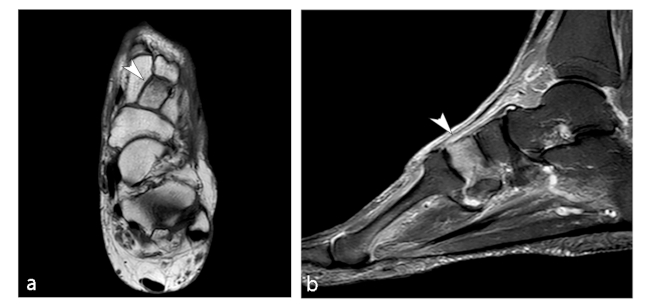

El astrágalo es el segundo hueso más grande del tarso y presenta una estructura que permite distribuir el peso corporal. La ausencia de inserciones musculares y escasas ligamentosas en este hueso hace que la vascularización extraósea sea menor que en otros huesos. Además, el 60% de su superficie presenta cartílago articular, con ausencia a nivel del cuello y parte posterior del cuerpo.16 Dentro del hueso, los territorios vasculares son autónomos, la cabeza y el cuello están bien vascularizados por ramas que penetran por la parte superior o inferior del cuello. Por el contrario, el cuerpo presenta una vascularización bastante pobre.17,18

La ON del astrágalo guarda una estrecha relación con los traumatismos; la necrosis atraumática solo representa un 10% de los casos.6,16 Existen dos lesiones traumáticas que potencialmente pueden desencadenar la aparición de la ON: fracturas del cuello del astrágalo y dislocación del astrágalo.17

Aunque no existe un sistema de clasificación específica, la ON del astrágalo exhibe un patrón característico de la enfermedad. Por lo general, aparece como un área de esclerosis en la cúpula del astrágalo que puede extenderse en el cuerpo talar, con posible colapso de la superficie articular y, en casos graves, la fragmentación de la cúpula del astrágalo y el cuerpo.

La RM es la técnica más sensible, especialmente en las primeras etapas, siendo de mayor ayuda diagnóstica cuando hay una alta sospecha clínica de NOA y los hallazgos radiográficos son normales (►Fig. 8).6,16